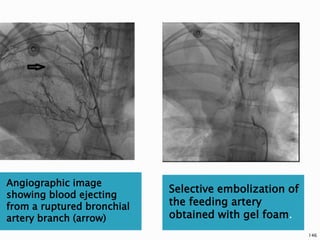

2.INTRACTABLE HEMOPTYSIS

 Bronchial artery angiography with

embolization has become a mainstay in the

treatment of intractable hemoptysis in

some patients with lung cancer.

 Major complications are rare and immediate

clinical success defined as cessation of

hemorrhage ranges in most series from 85%

to 100%, although recurrence of

hemorrhage ranges from 10% to 33%.

144

 Reports of neurological damage following

bronchial angiography indicate care in

avoiding obstruction of the artery of

Adamkiewicz.

145

Angiographic image

showing blood ejecting

from a ruptured bronchial

artery branch (arrow)

Selective embolization of

the feeding artery

obtained with gel foam.